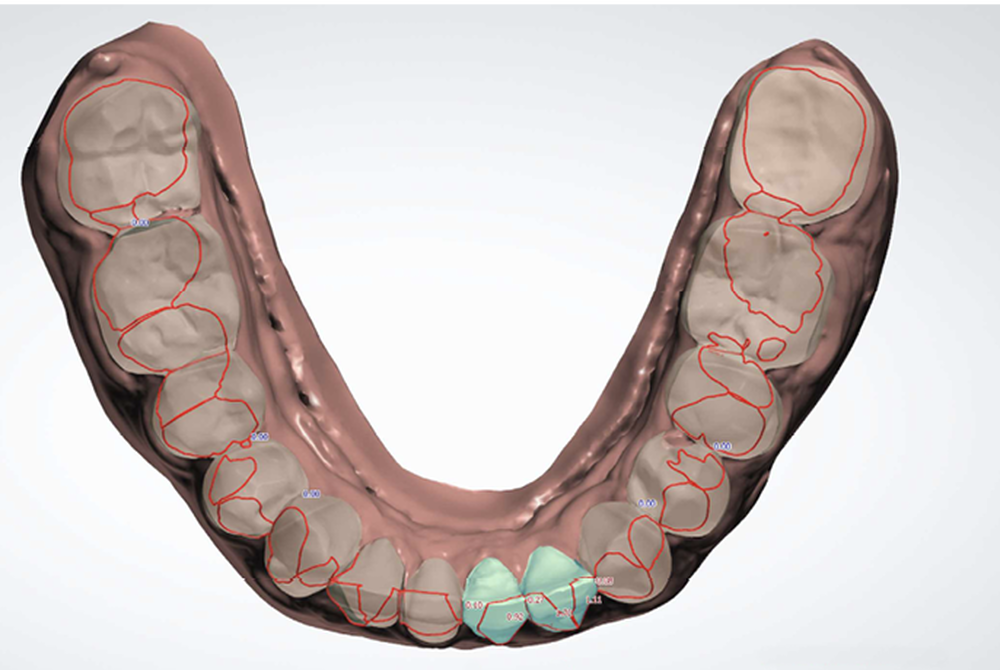

(fig. 4 à 10)

Le plan de traitement établi conjointement avec son chirurgien-dentiste traitant consiste à réaliser un alignement dentaire mandibulaire et à réaliser des extractions de 16 et 15 pour un remplacement par prothèse implanto-portée.

La durée orthodontique prévue est de neuf mois, avec comme contrainte principale l’absence de possibilités de modification des formes d’arcades.

Le gain de place se fera par des réductions interproximales sur la zone incisivo-canine mandibulaire.